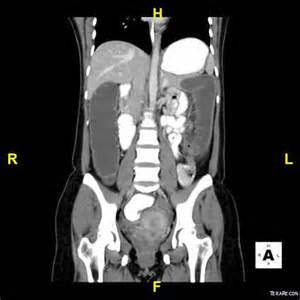

Crohn xəstəliyinin diaqnozu üçün hansı müayinələr vacibdir?

Kolonoskopiya və biopsiya ilə, KT, nəcis analizi